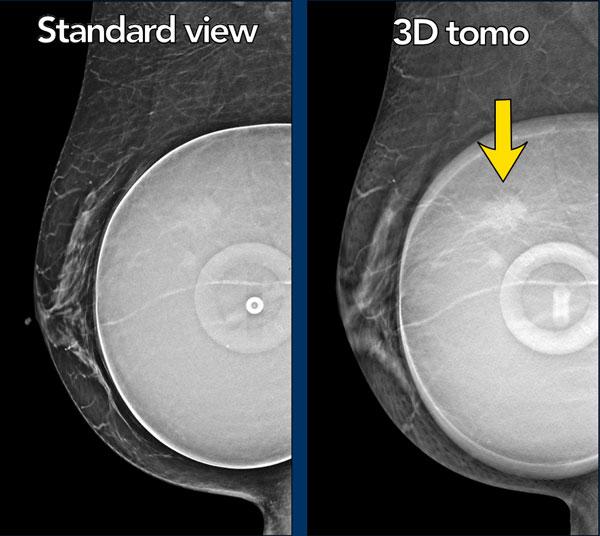

Người phụ nữ này có túi ngực chứa nước muối sinh lý và cho thấy hình ảnh van bơm dạng đĩa dẹt.

Có một khối, rõ hơn trên hình ảnh chụp cắt lớp tổng hợp (lát cắt 56 trong tổng số 73).

Đây là một khối có bờ tua gai.

Giải phẫu bệnh: ung thư tiểu thùy xâm nhập độ 2 và ung thư tiểu thùy tại chỗ (LCIS).